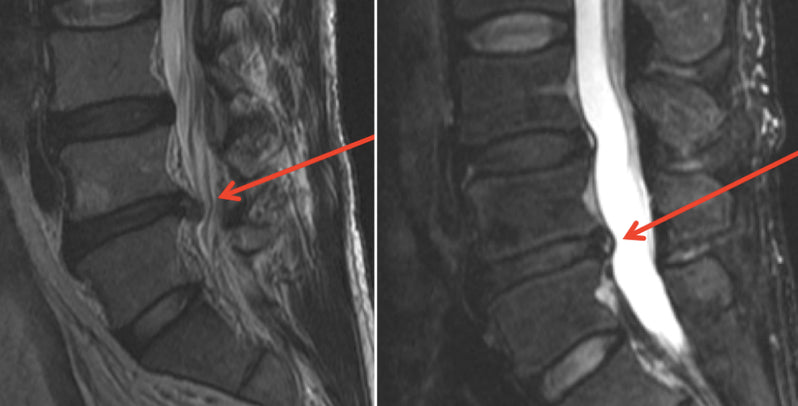

Here is an example – The patient was a 53-year-old active duty Marine Corps Master Gunnery Sergeant with a history of repetitive low back pain after a sports injury 10 years prior. He was told that he had a disk rupture with stenosis, and surgery was recommended. He underwent 1 year of physical therapy and other conservative therapies and had no improvement. His left leg started hurting, and he stated that his pain was getting worse and that it hurt to sit and lie down. An MRI was obtained and is shown below:

The comparison of the before and after MRIs are shown below. The herniation is depicted by the arrows.